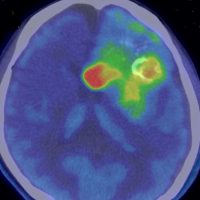

- 生検術を行う時には,perfusion MRIやメチオニンペットがターゲットを絞るのに有効です

メチオニンペット Met-PET

11C-メチオニンという放射性物質を静脈から注射して,脳のPET(ポジトロン断層撮影)をします。メチオニンの取り込みが高いところが赤く描出されます。グリオーマと炎症性疾患や壊死などとの鑑別に迷った時に用いられることがあります。グリオーマでは,悪性度の高いもの,乏突起膠腫に取り込みが高く見られますが,病理診断を超える価値はありません。

これを見たからといってグリオーマの治療方法が変わるわけではありませんから,保険診療は認められていません。自己負担で6万円以上はかかるでしょう。